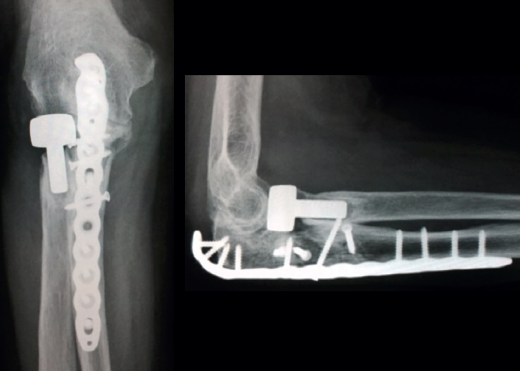

Las placas colocadas en la superficie posterior del cúbito son el sistema de fijación recomendado, proporcionando una fijación más resistente que los cerclajes con agujas de Kirschner y además permiten la fijación adicional de los fragmentos óseos y de la coronoides con tornillos o placas ortogonales en las superficies medial o lateral en los casos con gran conminución metafisaria(1,2,17). Las placas especialmente diseñadas de olécranon (Figuras 5 y 6) o las placas de compresión dinámica de contacto limitado (LC-DCP) de 3,5 mm conformadas para adaptarse a la morfología del cúbito son preferibles a las placas semitubulares, al aportar una fijación más estable(2,18,19).

Cuando la fractura del olécranon incluye una fractura de la coronoides, la reducción y la fijación de esta es condición imperativa para conseguir la estabilidad humerocubital (Figuras 7, 8 y 9). La reducción puede llevarse a cabo a través de la fractura del olécranon o por medio de un abordaje medial, separando o a través de la musculatura flexora/pronadora, teniendo identificados y protegidos el nervio cubital y el fascículo anterior del ligamento colateral medial. En los casos en los que es necesario realizar la sustitución de la cabeza del radio por una prótesis, también es posible el acceso lateral a la fractura de la coronoides. En general, el fragmento permite la fijación con tornillos desde posterior a anterior, a través de la placa posterior o independientes de esta, o en ocasiones desde anterior a posterior. La utilización de placas de 2,7 mm o específicas de coronoides, y técnicas de suturas no reabsorbibles atadas sobre el cúbito proximal o sobre la placa de fijación del cúbito son otras opciones(13,17). Para los grandes defectos óseos o fracturas irreconstruibles de la coronoides, se han descrito injertos óseos de la cresta ilíaca e injertos osteocondrales de la cabeza del radio con resultados impredecibles debido a la osificación heterotópica y a la reabsorción ósea del injerto(20,21).

Tratamiento de la fractura y/o luxación de la cabeza del radio

Las opciones de tratamiento para las fracturas de la cabeza del radio en este tipo de lesiones incluyen la reducción y la fijación interna, la artroplastia y la escisión de pequeños fragmentos. La clasificación de Mason(23) y el número de fragmentos son los factores que condicionan el tratamiento, que en última instancia dependerá de la decisión del cirujano (Figuras 10 y 11). Una reducción o una fijación inadecuadas pueden acompañarse de más complicaciones que la escisión y sustitución por una prótesis al acabar en pseudoartrosis o consolidaciones viciosas que limitan la pronosupinación del antebrazo y producen dolor(3).